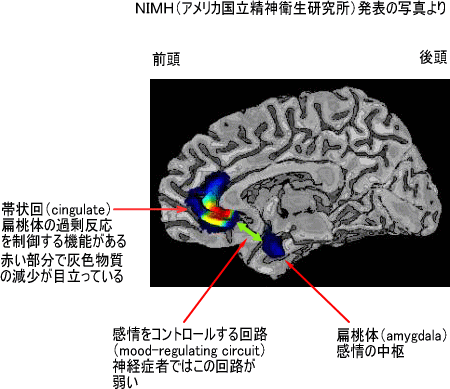

今日の精神保健学の講義で、情動と大脳の関係について触れた。最近のいわゆるキレ易い若者が辺縁系下部にある扁桃体に問題があり、さらに感情を制御する前頭前野の抑制力が落ちていることを説明した。そう話している間に、学生たちはいつもながらあっちでペチャペチャ、こっちでクチャクチャの状態・・・溜息。

実は聖書で言う魂(Soul)は、知性・感情・意志からなるが、その大脳の対応部位はそれぞれほぼ、海馬・扁桃・前頭葉である。海馬は記憶を、扁桃を含む辺縁系は情動を、前頭葉は意志や意欲と関係する。そして扁桃で生じた感情は前頭葉の制御を受けるわけだが、最近の若者(ばかりでもないが・・・)はその制御が弱いのだ。